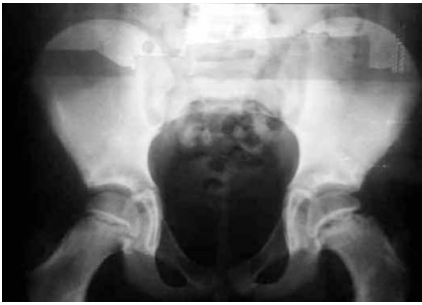

Um adolescente, 12 anos de idade, relatou sentir

dor no quadril esquerdo há 3 meses, com piora progressiva.

Exame físico com rotação externa do quadril esquerdo

em decúbito dorsal, teste de mobilidade com limitação

da rotação interna. Sinal de Trendelenburg ausente.

IMC zcore +2.8. Realizado raio X de quadril.

Com base nessa situação hipotética, assinale a alternativa que apresenta a hipótese diagnóstica adequada.